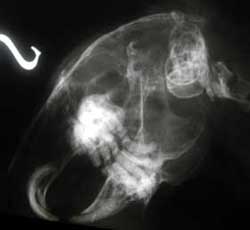

Immagine rx di ascesso sottomandibolare

Nei casi più avanzati di malattia e necessario ricorrere ad estrazioni chirurgiche di elementi dentali ed ad altre chirurgie invasive per il controllo di ascessi dentali.